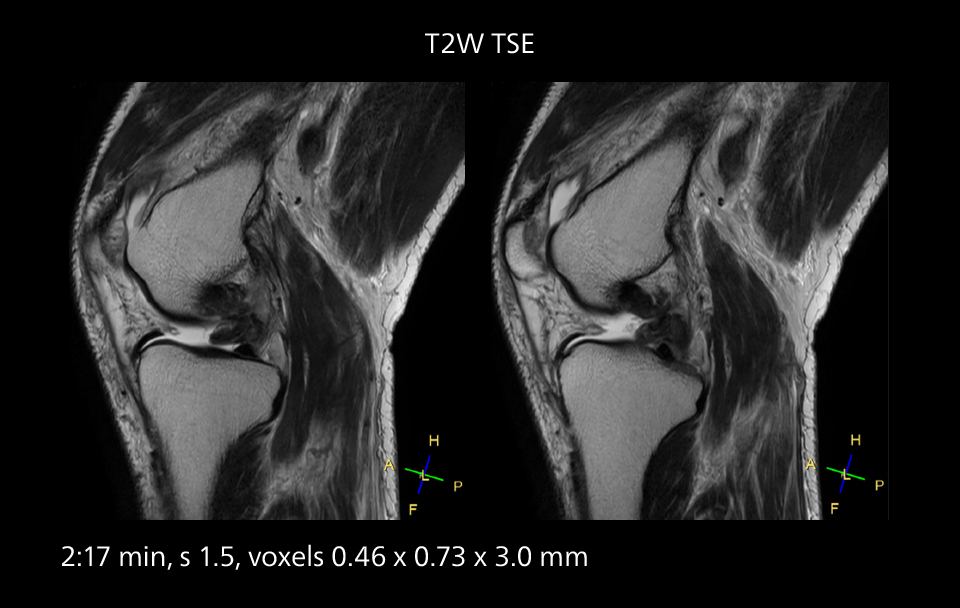

These images of an old cerebral infarction demonstrate the speed and image quality after upgrading to Elition X.